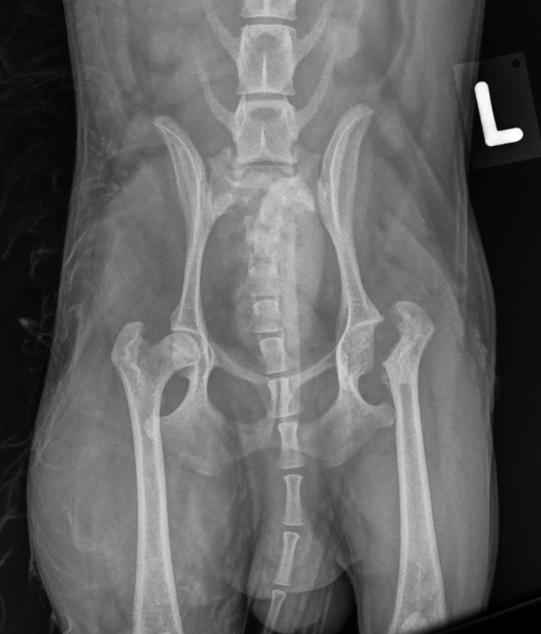

Im Untersuch scheint die Hüftregion des Junghundes schmerzhaft. Die Ursache dafür ist in einem Röntgenbild klar ersichtlich: Der linke Oberschenkelkopf escheint stark verändert; er ist nicht wie sein rechtes Gegenstück schön rund, sondern etwas eckig und von verminderter Röntgendichte. Mero leidet an einer sogenannten Aseptischen Femurkopfnekrose (Morbus Legg-Calvé-Perthes).